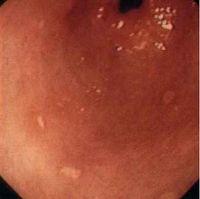

黄色瘤即黄瘤病(Xanthomatosis)的黄瘤是含脂质的组织细胞和巨噬细胞局限性聚集于真皮或肌腱等处形成的黄色橘黄色或棕红色的丘疹、结节或斑块,常伴有血脂质和其他系统的异常而出现一系列临床症状。

一种少见的脂类代谢性疾病。由于含有脂类的细胞在真皮或皮下组织内聚集,常在皮肤表面形成黄色的瘤状损害,故名。该病的皮疹形态和分布多种多样。主要有结节性、扁平性、发疹性及腱性4种类型。该病可以合并血脂代谢异常。有的病例有家族性,有的有系统性病变,如脂类沉积于心血管可产生动脉硬化和小血管的栓塞。有的还可合并或继发于其他疾病,如糖尿病、肝病、肾病等。当发现皮肤黄色瘤时,首先应确定其为单纯的皮肤型,还是高脂蛋白血症的皮肤表现。仅有皮肤损害而不侵犯内脏的病例,一般预后良好。

发病机制尚不完全清楚。黄色瘤中以睑黄瘤及扁平黄瘤比较常见,呈淡黄色、柔软、略高出皮肤表面、与正常皮肤分界清楚、呈小片状或米粒大小的斑块,睑黄瘤常常发生上眼睑与内眦部位,而下睑较少发生。表皮正常或压迫性变薄,可见真皮中泡沫细胞或黄瘤细胞浸润,有Touton多核巨细胞与胆固醇和胆固醇酯沉积,早期还可有相关细胞损害,消退期多为成纤维细胞取代。

1.扁平黄瘤(plane xanthoma) 较常见,好发于颈肘窝、腋窝、股内侧及躯干等部位,常有高脂蛋白血症,黏膜往往不受损害。

2.睑黄瘤(lid xanthoma) 最常见青中年女性较多见,经常发生在眼睑内眦处,可单发或多发,逐渐发展形成较大范围的黄色瘤,也可与其他型黄色瘤伴发。

3.结节性黄瘤(tuberous xanthoma) 多发于肘膝关节,皮疹隆起呈圆形,橘黄色结节状较硬,可单发也可多发大者直径可达7~8cm,呈巨大结节性黄色瘤,可伴有高脂蛋白血症及冠心病等异常

4.发疹性黄瘤(eruptive xanthoma) 多为针头大小的皮肤损害,小黄瘤呈黄棕色,可迅速成群发生,并有瘙痒皮疹,数周后可自行消散,多发生于臀部、臂部、大腿屈侧与股股沟等部位。本型多有高脂血症的高乳糜微粒血症。

5.腱黄瘤(tendon xanthoma) 发生在肌腱上的黄瘤可为丘疹或结节状,多发于手足背伸肌腱及跟腱部位。血脂可升高也可在正常范围内。

6.掌黄瘤(palmar xanthoma) 发生在沿掌纹和手指掌面纹理分布的扁平黄色瘤常很微细,呈线状分布,多有高脂血症

7.播散性黄瘤病(disseminated xanthoma) 比较少见皮损,呈多发性小黄丘疹或小黄结节成群分布于颈、腋肘腘窝、腹股沟等部位。